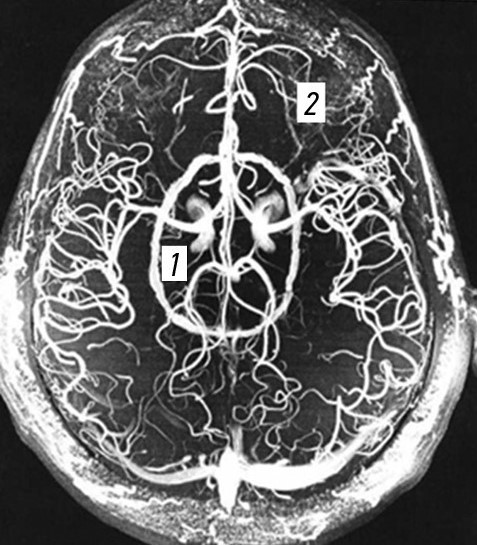

На рис. 2 представлены зоны поражения сосудов ГМ при огнестрельных проникающих черепно-мозговых ранениях.

Рис. 2. Магнитно-резонансная ангиография головного мозга с зонами расположения сосудов: 1 — сосуды подкорковых образований, желудочков и ствола головного мозга; 2 — сосуды коры головного мозга.